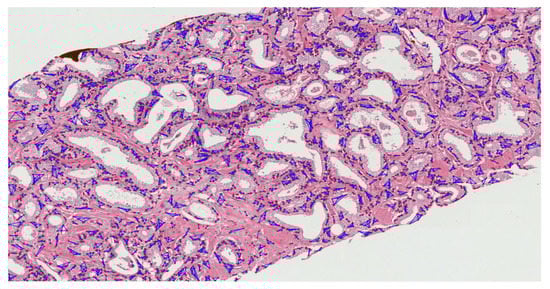

A total of 900 H&E-stained patch images of size 512 × 512 pixels were generated by tiling the pathology annotated slides. Furthermore, the acquired samples were divided equally into three cancer grades (300 grade 3, 300 grade 4, and 300 grade 5). For supervised classification, the dataset was divided into two subsets: train set (80%) and test set (20%). On the other hand, unsupervised classification was performed using the whole dataset. Examples of histopathological images of datasets 1 and 2 are shown in Figure 1. The binary classification was defined (grade 3 vs. grade 5) as was multiclass classification (grade 3 vs. grade 4 vs. grade 5). Appendix A, Figure A1, Figure A2 and Figure A3 show the illustration of the Gleason grading process. Each of the grades is assigned according to the Gleason grading system as follows:

Figure 1.

Histologic findings for each grade of prostate cancer. (a–c) Dataset 1: grade 3, grade 4, and grade 5, respectively. (d–f) Dataset 2: grade 3, grade 4, and grade 5, respectively.

- Grade 3: Gleason score 4 + 3 = 7. Distinctly infiltrative margin.

- Grade 4: Gleason score 4 + 4 = 8. Irregular masses of neoplastic glands. Cancer cells have lost their ability to form glands.

- Grade 5: Gleason score 4 + 5, 5 + 4, or 5 + 5 = 9 or 10. Only occasional gland formation. Sheets of cancer cells throughout the tissue.